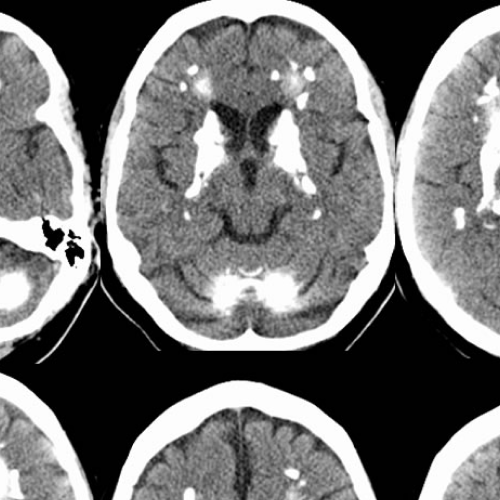

At S9 Teleradiology, we bring high-quality radiology reporting to your diagnostic center—whether you’re in a bustling city or a remote town. Powered by a team of experienced and qualified radiologists, we provide fast, reliable, and expert interpretations of X-rays, CT scans, MRI, and advanced studies—all delivered through secure tele-reporting platforms.

- CT Scan

Telereporting of Cross-Sectional Studies: CT & MRI

Wide range of CT and MRI scans are reported 24 x7 hours of 365 days.